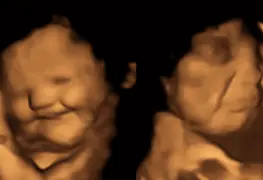

Investigación confirmó que los fetos pueden sentir gustos durante la gestación

Los investigadores estudiaron a unas 100 mujeres embarazadas y a sus bebés por nacer